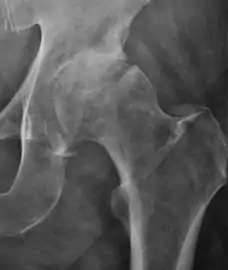

X-Ray

Projectional radiography ("X-ray") is currently useful not only in older people in whom osteoarthritis of the hip is suspected but also in younger people without osteoarthritis, who are being evaluated for femoroacetabular impingement (FAI) or hip dysplasia.[1]

Plain radiography allows us to categorize the hip as normal or dysplastic or with impingement signs (pincer, cam, or a combination of both). Besides these, pathologic processes like osteoarthritis, inflammatory diseases, infection, or tumors can also be identified (Figure 1).[1]

- Osteoarthritis

In adults, one of the main indications for radiographs is the detection of osteoarthritic changes (Figure 1(e)). Nevertheless, radiographs usually detect advanced osteoarthritis that can be graded according to the Tönnis classifications. The grading system ranges from 0 to 3, where 0 shows no sign of osteoarthritis. Intermediate grade 1 shows mild sclerosis of the head and acetabulum, slight joint space narrowing, and marginal osteophyte lipping. Grade 2 presents with small cysts in the femoral head or acetabulum, moderate joint space narrowing, and moderate loss of sphericity of the femoral head. Grade 3 is the severest form of osteoarthritis, which manifests as severe narrowing of the joint space, large subchondral cyst with productive bone changes that may lead to deformity of the bone components of the joint, while secondary osteoarthritis due to calcium pyrophosphate deposition can be diagnosed when calcification of hyaline cartilage and fibrocartilage is detected.[1]